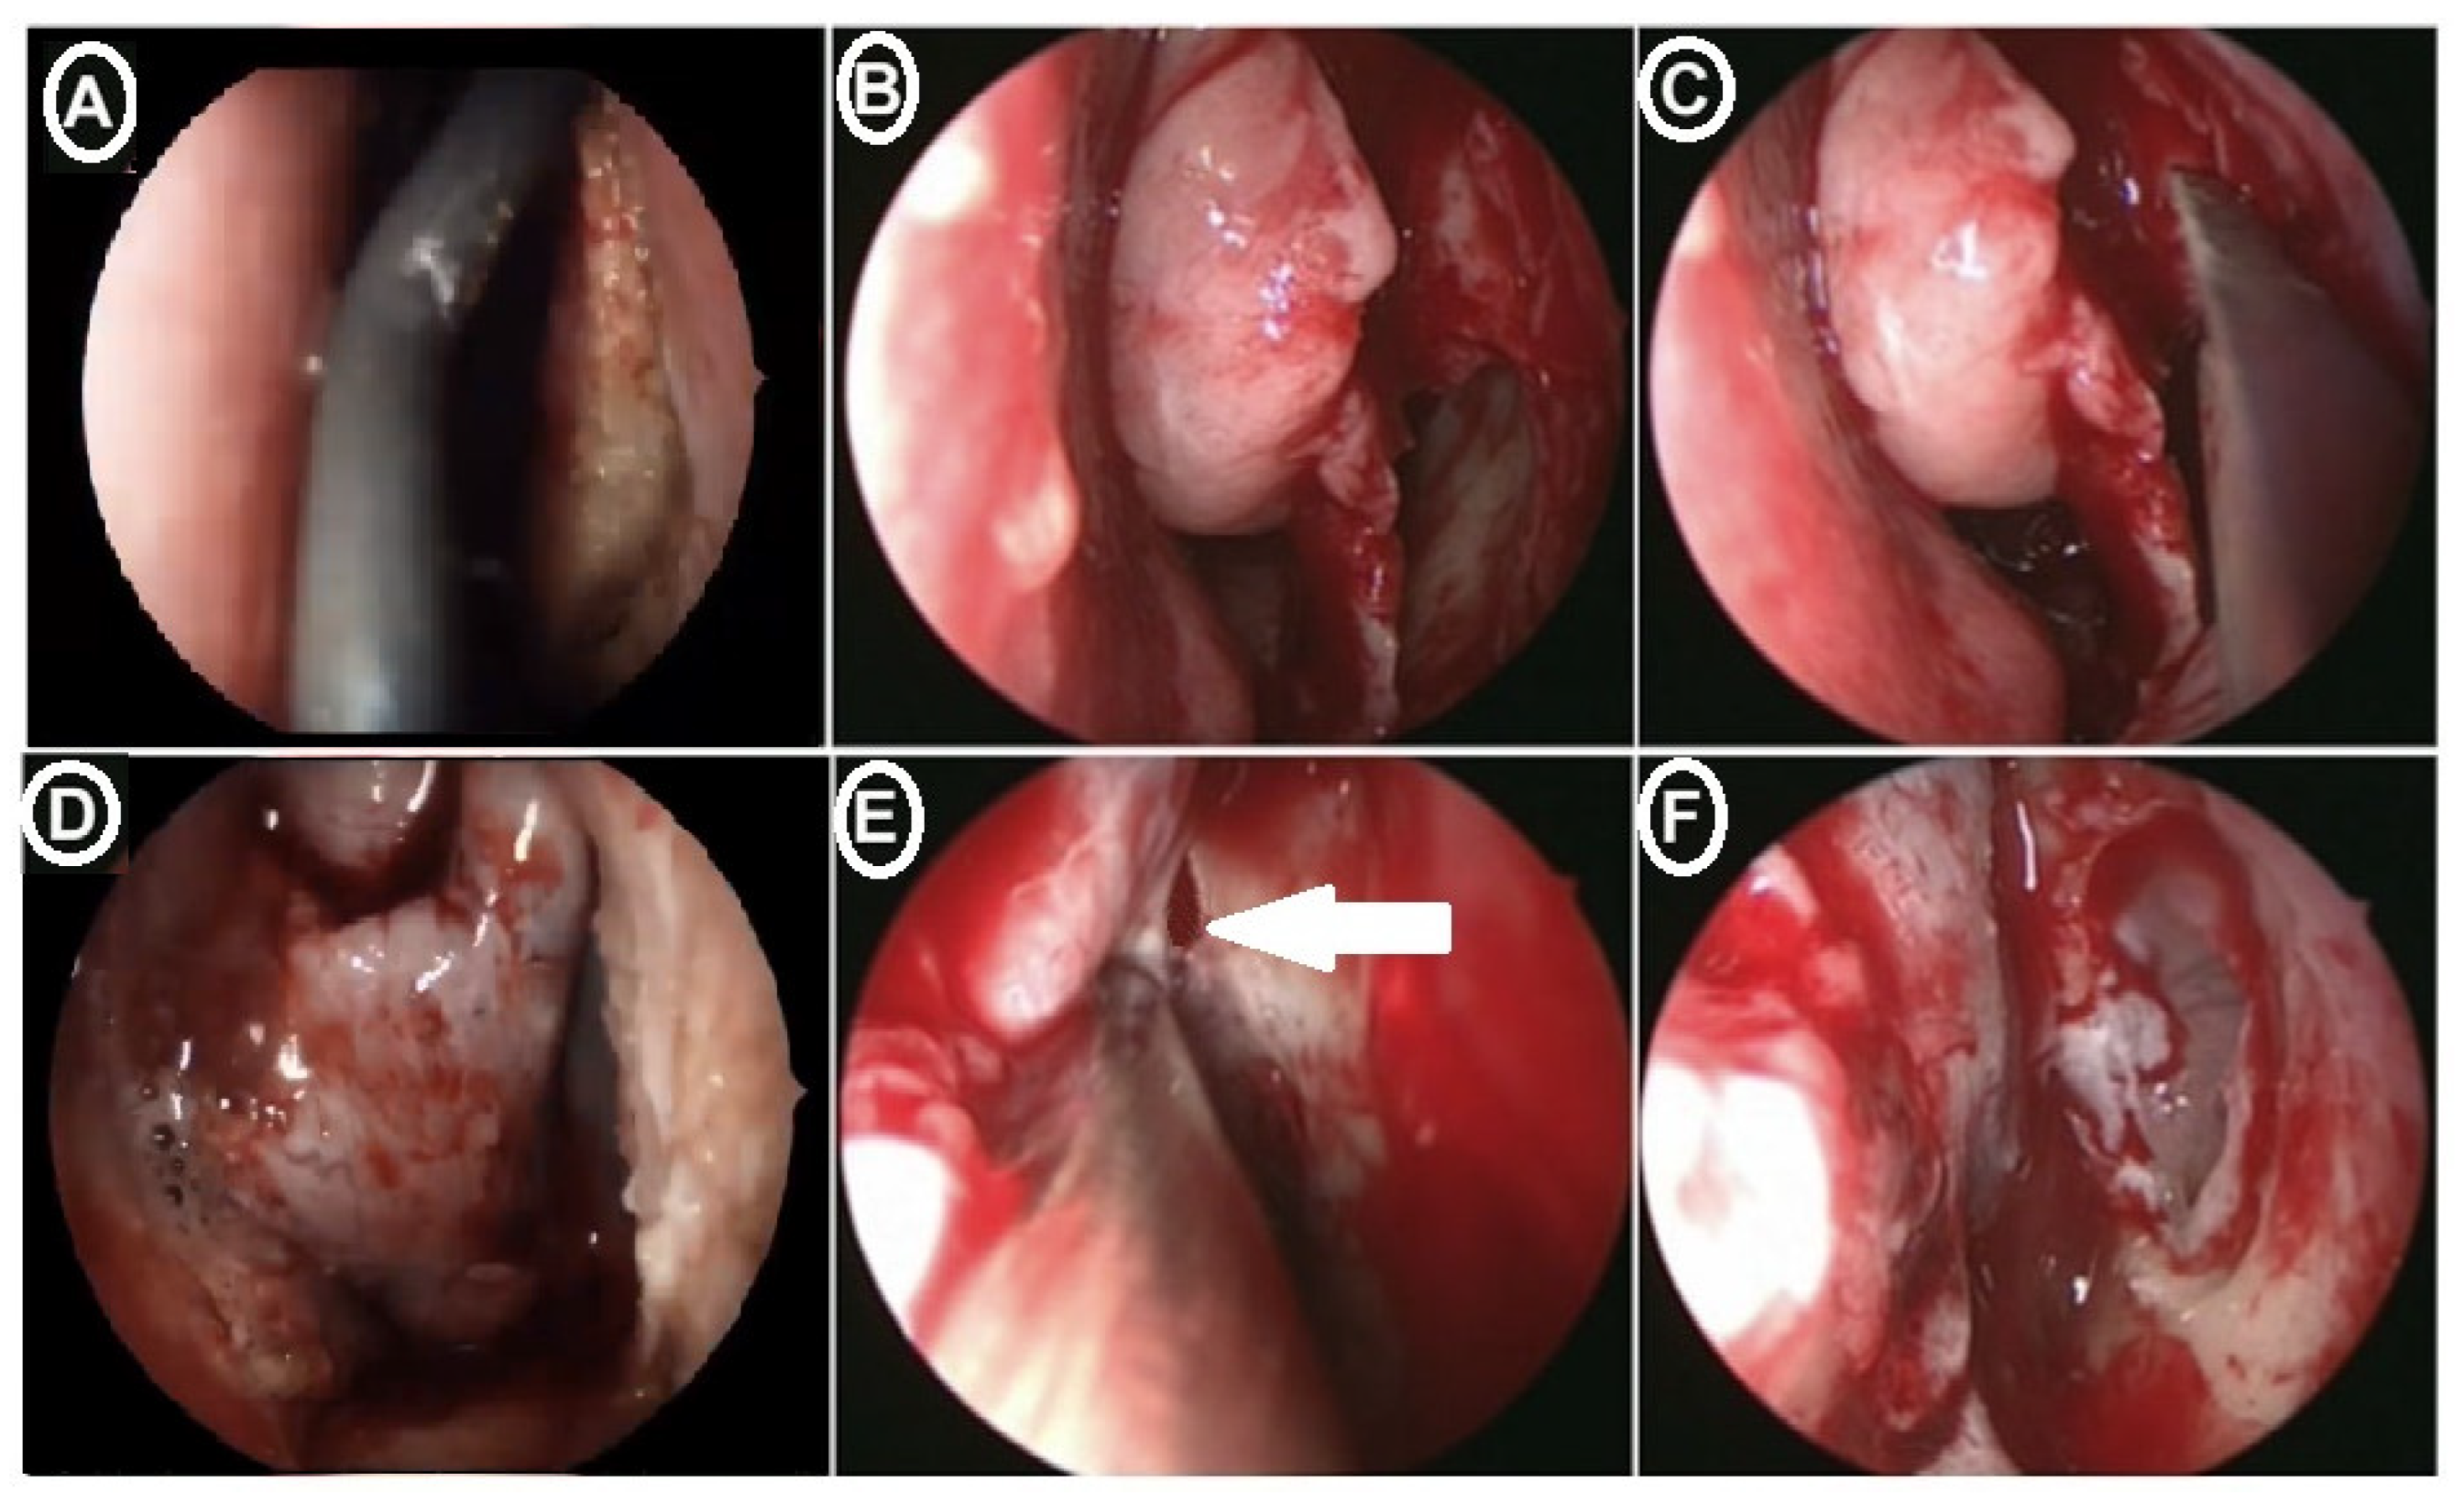

Surgical Technique